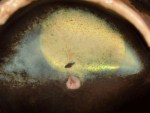

(click to enlarge) Canine retina two years post injection. Retinal photograph taken more than two years after subretinal injection of AAV2-hRPE65v2 in the second eye of a dog model of Leber's congenital amaurosis due to RPE65 mutations. The AAV-exposed portion of the retina, with the overlying inner retinal blood vessels, appears yellow due to reflective changes in the underlying tapetum.